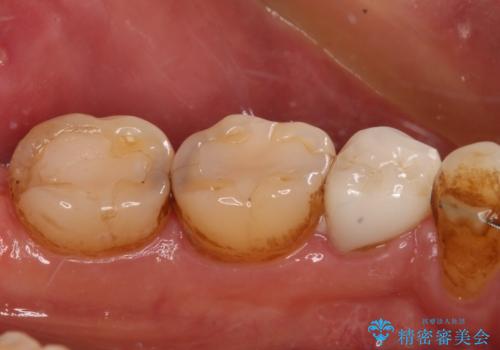

- 奥歯がしみるとのことで来院された患者様です。

診査をしたところ、目視でも明らかな、とても大きなむし歯があありました。

既に治療により詰め物が装着されている歯であったため、オールセラミッククラウンによる補綴治療を選択することとしました。